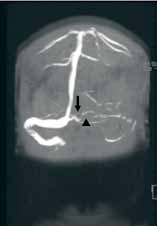

Based on the patient’s history of ET and postpartum state, there was a high suspicion for cerebral venous thrombosis (CVT). Magnetic resonance imaging/magnetic resonance venography (MRI/MRV) of the brain was obtained, which revealed near-complete thrombosis of the vein of Galen and straight sinus (Figure). Neurology and hematology services were consulted emergently, and the patient was started on a heparin drip and admitted to the neurosurgical intensive care unit. Hydroxyurea was also given for cytoreduction, and platelets normalized to 305 x 109/L within 1 day of treatment. The patient’s neurological examination remained nonfocal, her headache gradually resolved, and she was discharged on hospital day 3 on oral anticoagulants.